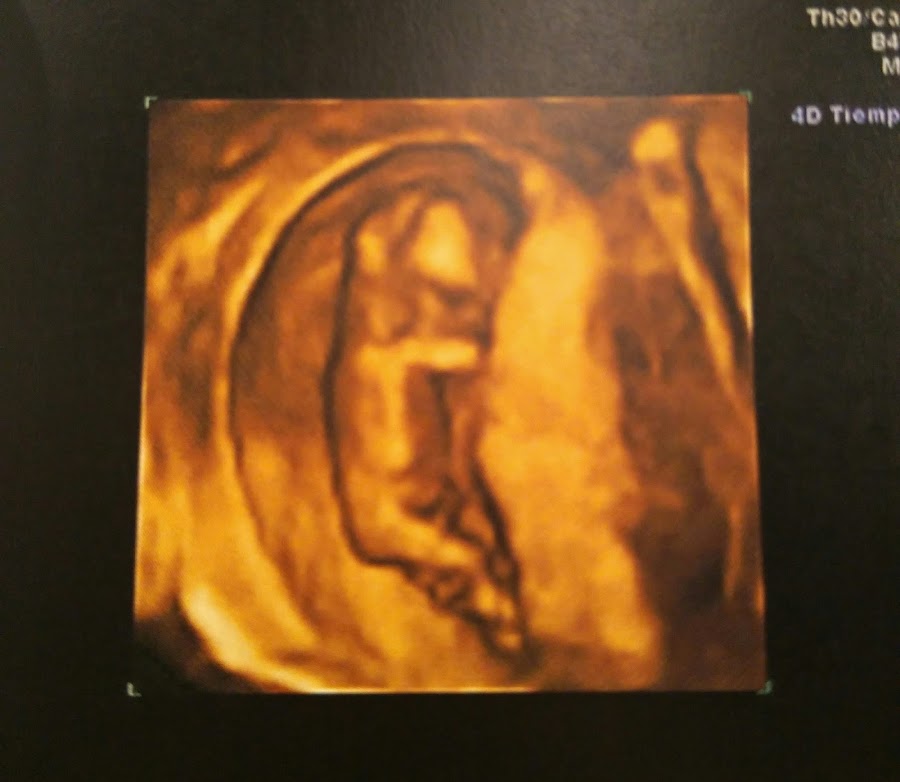

Y aquí está mi bolita!! Con una 4d y todo. Estoy eufórica, feliz, llena de amor y de mucha tranquilidad. Ayer estuve en la ecografía de las 12 semanas, en la que junto con la analítica ven el riesgo de síndromes como el Down, Edwars, etc. Fue toda una experiencia.

Según me echó el gel y puso el ecógrafo en mi tripa, ahí estaba, muy grande y muy formado desde la última vez. No había pasado ni 10 segundos y la doctora dijo que veía el pliege nucal muy bien. Empecé a llorar. Pensé en reprimirme y no comportarme como una primeriza sensiblona. Pero se me empezaron a caer las lágrimas y no pararon hasta el final. El Señor J también lloró y mi madre, creo que de verle a él.

La bolita no paró de moverse, estiraba las piernas y se tocaba la cara, no se lo puso fácil a la doctora, pero lo vio todo fenomenal.

Al final del todo le pregunté si se veía el sexo, y me dijo que me daba un 70% de probabilidades de que fuera una niña. Más lágrimas. Aunque no me haré más ilusiones.